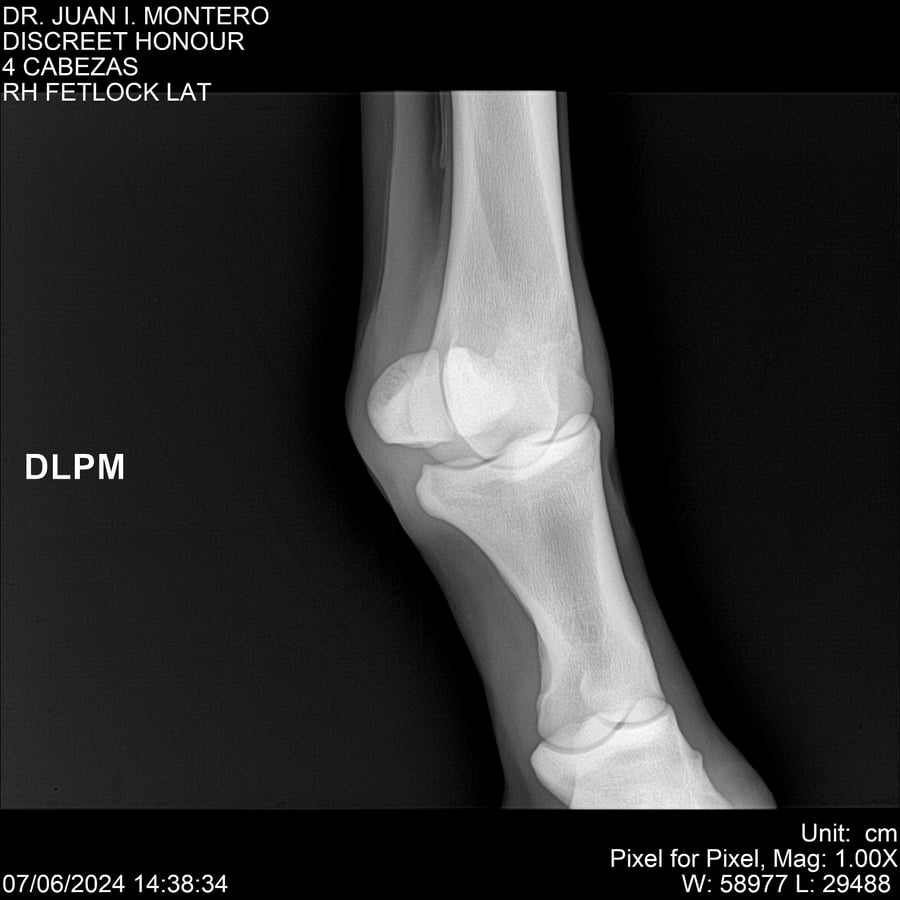

LOTE 6, DISCREET HONOUR 🔥 🔥 🔥 Lote Anterior Volver al remate Lote Siguiente Ficha Contacto Montevideo - Ficha del Lote Identificador: #281093 Categoría: Yeguarizos Montevideo - 82 Visualizaciones ClicData Contacto Empresa: Abelenda N. R., Walter Hugo Nombre*: Teléfono* : E-mail* : Mensaje Enviar Registrese gratis Este contenido Exclusivo está disponible sólo para usuarios registrados Ingresar